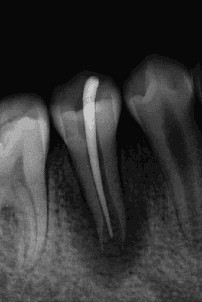

通过牙髓再生治疗,促进牙髓坏死的年轻恒牙牙根进一步发育,牙髓活力测试呈阳性 。

术后6个月